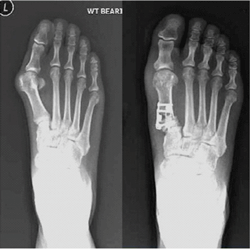

[사진. 미니금속판 수술 전후 모습]

과정은 먼저, 엄지발가락 부위를 절개한 후, 엄지발가락 하단 부위인 제1중족골 부위 1~2곳을 절골해 엄지발가락의 위치를 바로잡는다. 이 때, 뼈를 고정시키는 과정에서 기존의 금속핀 대신 미니금속판이 사용된다. 수술 부위에 맞는 미니금속판을 선택해 부착하고 같은 재질의 핀을 박아주면 수술이 끝난다. 미니금속판은 뼈가 붙고 난 뒤에도 제거하지 않아도 되므로 2차 수술 또한 하지 않는다.

기존의 절골술은 휘어진 엄지발가락의 뼈를 돌려서 제자리를 잡아준 후 고정을 위해 핀을 사용한다. 이 때 사용된 핀은 제거를 해야 하기 때문에 약 6주 후 또 한 번 수술을 해야 하는 번거로움이 있었다. 물론 녹는 핀을 사용하거나, 핀 고정을 하지 않는 수술도 존재하지만, 이는 무지외반증이 비교적 심하지 않거나 골질이 좋은 환자의 경우에만 해당되어 무지외반증이 심한 환자의 경우, 2차 수술은 불가피했다.